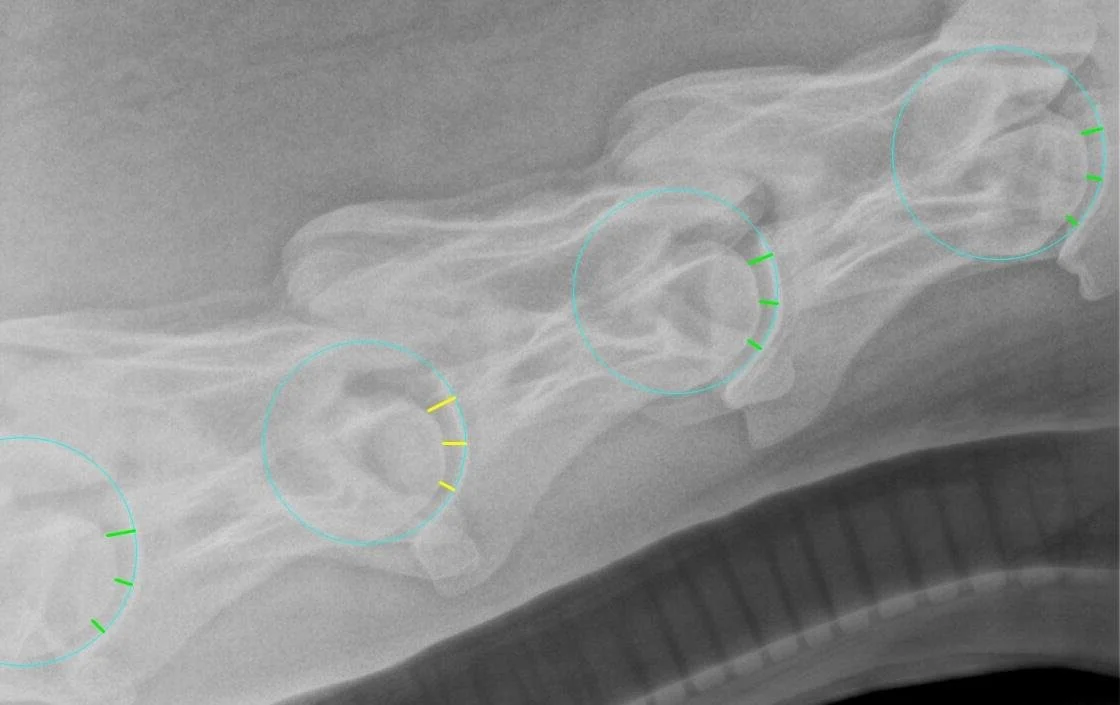

Our “Equine Cervical Gap Metric” is loosely based (or inspired by) the publication with clickable link in our report, namely, Veraa et al. But we compute the measure a bit differently. We fit a circle to the proximal joint surface of each visible vertebral body and measure the length of the joint space along 3 radial lines from the center of the fit circle. We then express the size of the joint space (or “gap”) as the ratio of this gap length over the radius of the circle, formulated as a percentage.

In reviewing thousands of images, it was decided to ignore the top-most gap measure, as the shape of the condyle is variable there, and so at present we use only the lower two gap measures - we average them to result in our “cervical gap metric” - a single number for each joint.

Example: Green gaps are in the “normal” range, Yellow GAPS are Larger than normal, and red gaps are smaller than normal. The histogram below is for these 4 joints.

In the image above, you see the circles that are fit to the geometry of the vertebral bodies and the gaps measured along the radial direction from the center of the circle. Currently we ignore the upper gap, and average the lower two as a percentage of the radius of the circle to compute the cervical gap metric.